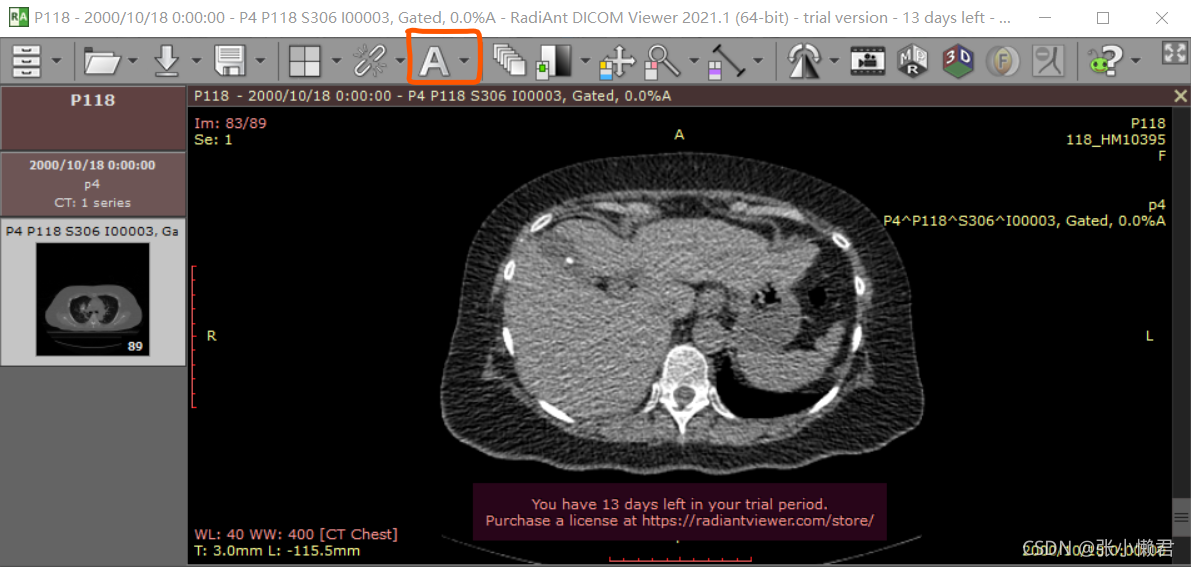

使用软件RadiAnt(RadiAnt DICOM Viewer | ZH (radiantviewer.com))读取DICOM文件信息。

点击 “A”标志的下拉按钮,点击“ show DICOM tag”

下一部分再来学习DICOM tag。